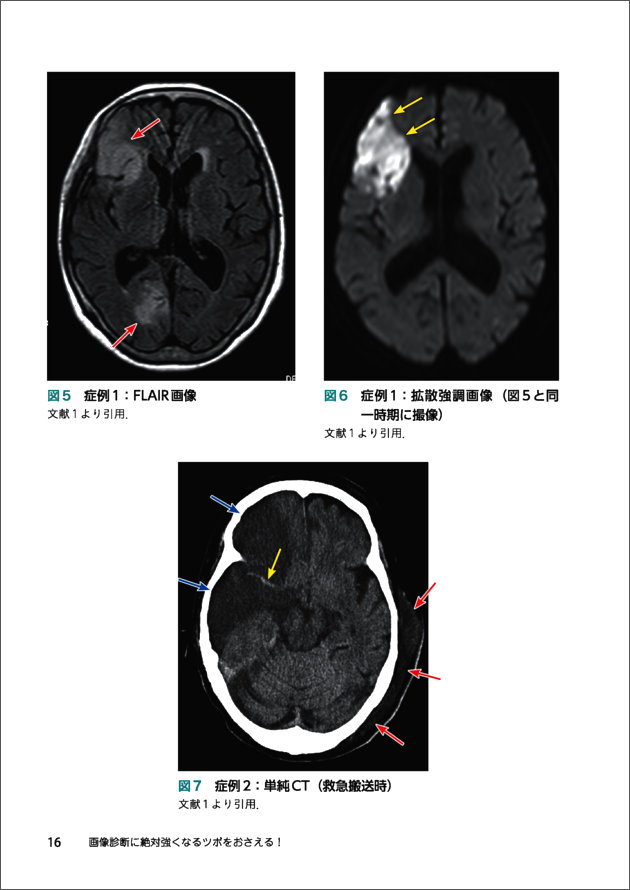

4 cortical SAH(convexal SAH)のツボ